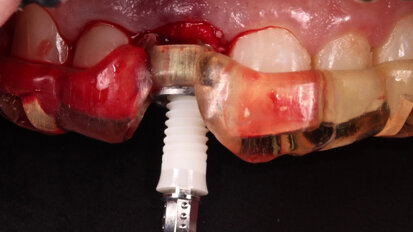

How to attract new patients by offering ceramic dental implants

The demand for ceramic implants is steadily increasing. In a forthcoming webinar, on Wednesday, 8 April, Dr Joan Pi-Anfruns will explain how dentists can ...